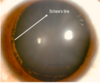

PIGMENTZ P - Pigment reversal sign (darker super angle) or Sampaolesi line I - Iris bowing posteriorly seen on AS OCT - more common in myopes G - Gonioscopy shows homogenous 360 degree pigmentation M - More pigmentation on corneal endothelium - Krukenberg's spindle E - Egger's line - pigment dispersion on anterior hyaloidocapsular ligament N - Near radial iris transillumination defects T - Thin retina - lattice degeneration Z - Zentmayer's line (Scheie's line) - pathognomonic - pigment on zonular attachments at lens equator and posterior capsule